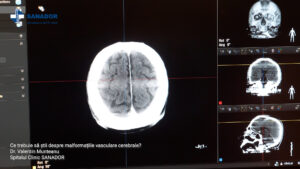

Malformațiile vasculare cerebrale sunt anomalii de dezvoltare a vaselor de sânge din creier.

Ele pot provoca hemoragii cerebrale și complicații severe. Multe dintre aceste malformații sunt congenitale, însă pot apărea și pe parcursul vieții ca urmare a unor leziuni cerebrale.

Tratamentul poate merge de la monitorizarea atentă la eliminarea chirurgicală a malformației sau embolizarea endovasculară a acesteia, cu scopul reducerii riscului de hemoragie cerebrală. Aflați mai mult despre malformațiile vasculare cerebrale de la Dr. Valentin Munteanu, medic primar neurochirurgie la Spitalul Clinic SANADOR.